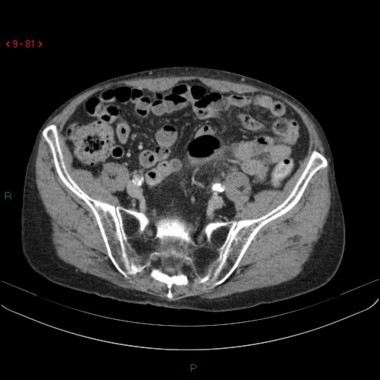

Sigmoïdite diverticulaire avec abcès

Case courtesy of Dr Sajoscha Sorrentino, Radiopaedia.org. From the case Diverticulitis with abscess